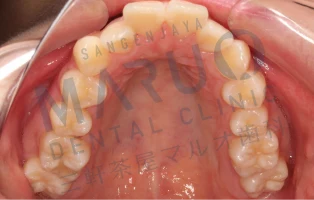

治療前

上の前歯が前に出ていることと歯のでこぼこを治したいとのことでした。

治療中

表側に装置をつける矯正を選択されました。上下左右の大人の歯を1本ずつ抜いて歯を並べ、前歯を後方に動かすスペースを確保しました。

動的治療終了時

動的治療期間は約2年6ヶ月でした。上の前歯の傾斜は改善し、歯のでこぼこは解消され、患者様に満足いただける結果となりました。

| 主訴 | 上の前歯が前に出ている 歯のでこぼこ |

|---|---|

| 診断名 | 上顎前突 叢生 |

| 年齢 | 13歳 |

| 治療に用いた主な装置 | マルチブラケット装置 |

| 抜歯部位 | 上下両側第一小臼歯 |

| 治療期間 | 2年6ヶ月 |

| リスク、副作用 | むし歯や歯周病、歯根吸収、治療後の後戻りの可能性があります |